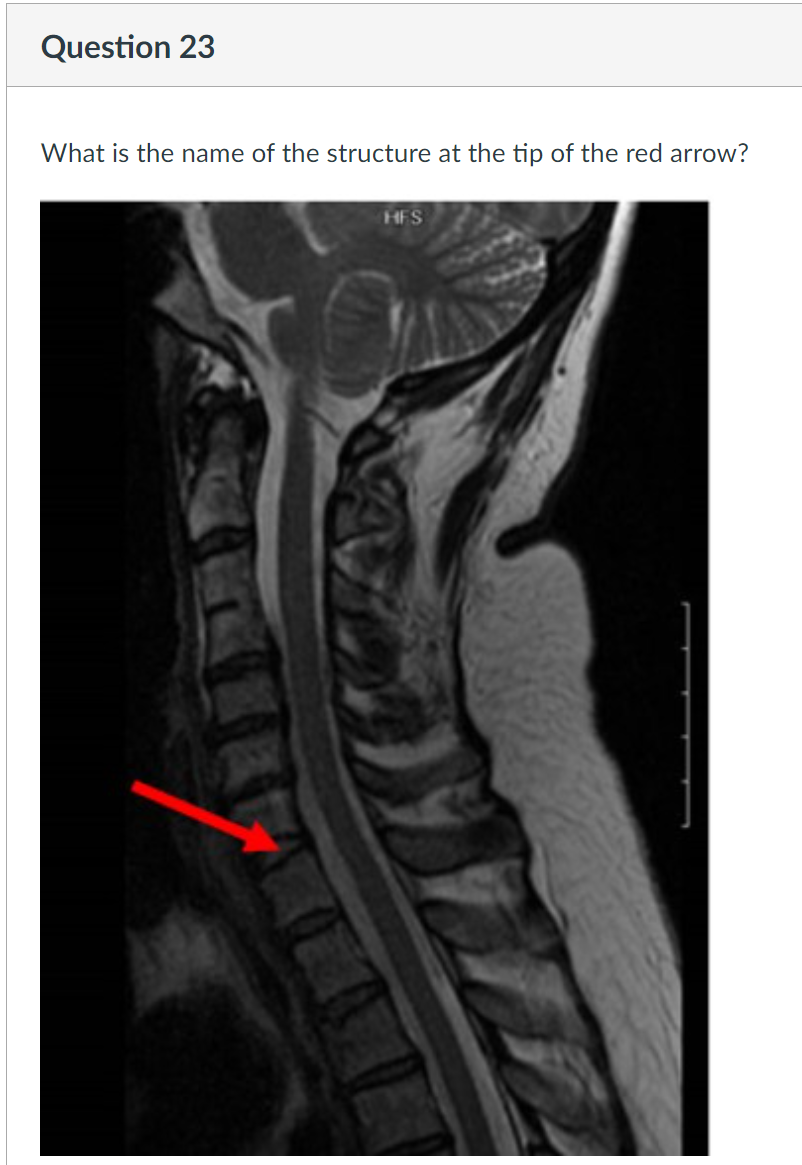

23

Q

A

dural cistern

cisterna magnum